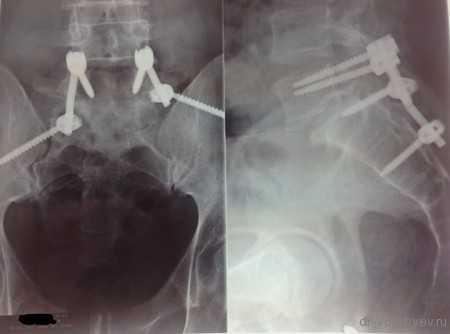

Рентген послеоперационной перкутанной ТПФ у пациентки с множественными переломами позвоночника

Пример лечения перкутанной транспедикулярной фиксацией спондилодисцита

После длительного курса лечения антибиотиками выполнена транспедикулярная фиксация системой viper II

Пациенту по поводу спондилолизного спондилолистеза выполнена декомпрессия и позвоночно-тазовая стабилизация системой expedium

Фото транспедикулярной фиксации позвоночника

Рентгеновского снимка после операции